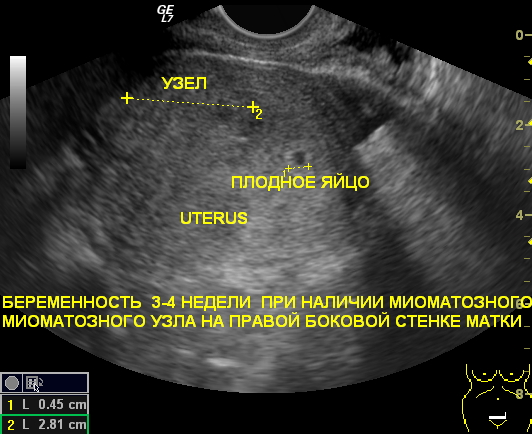

Миома при беременности и УЗИ

Регулярные ультразвуковые исследования миомы матки во время беременности имеют огромное значение. В период вынашивания малыша уровень эстрогена в организме возрастает, что приводит к активному делению клеток в тканях матки. Это может стать причиной появления миомы. Кроме того, уже существующие миомы могут начать увеличиваться в размерах. Поэтому проведение ультразвуковых исследований во время беременности становится крайне важным.

Миома во время беременности

Крупные опухоли могут существенно усложнить процесс родов. Они могут вызывать кровотечения в процессе родов и затруднять прохождение ребенка через родовые пути. Также возможно физическое сжатие плода. Кроме того, миомы могут нарушать работу плаценты, что приводит к недостаточному поступлению питательных веществ к ребенку. Именно поэтому важно проводить регулярные обследования на наличие опухолей во время беременности.